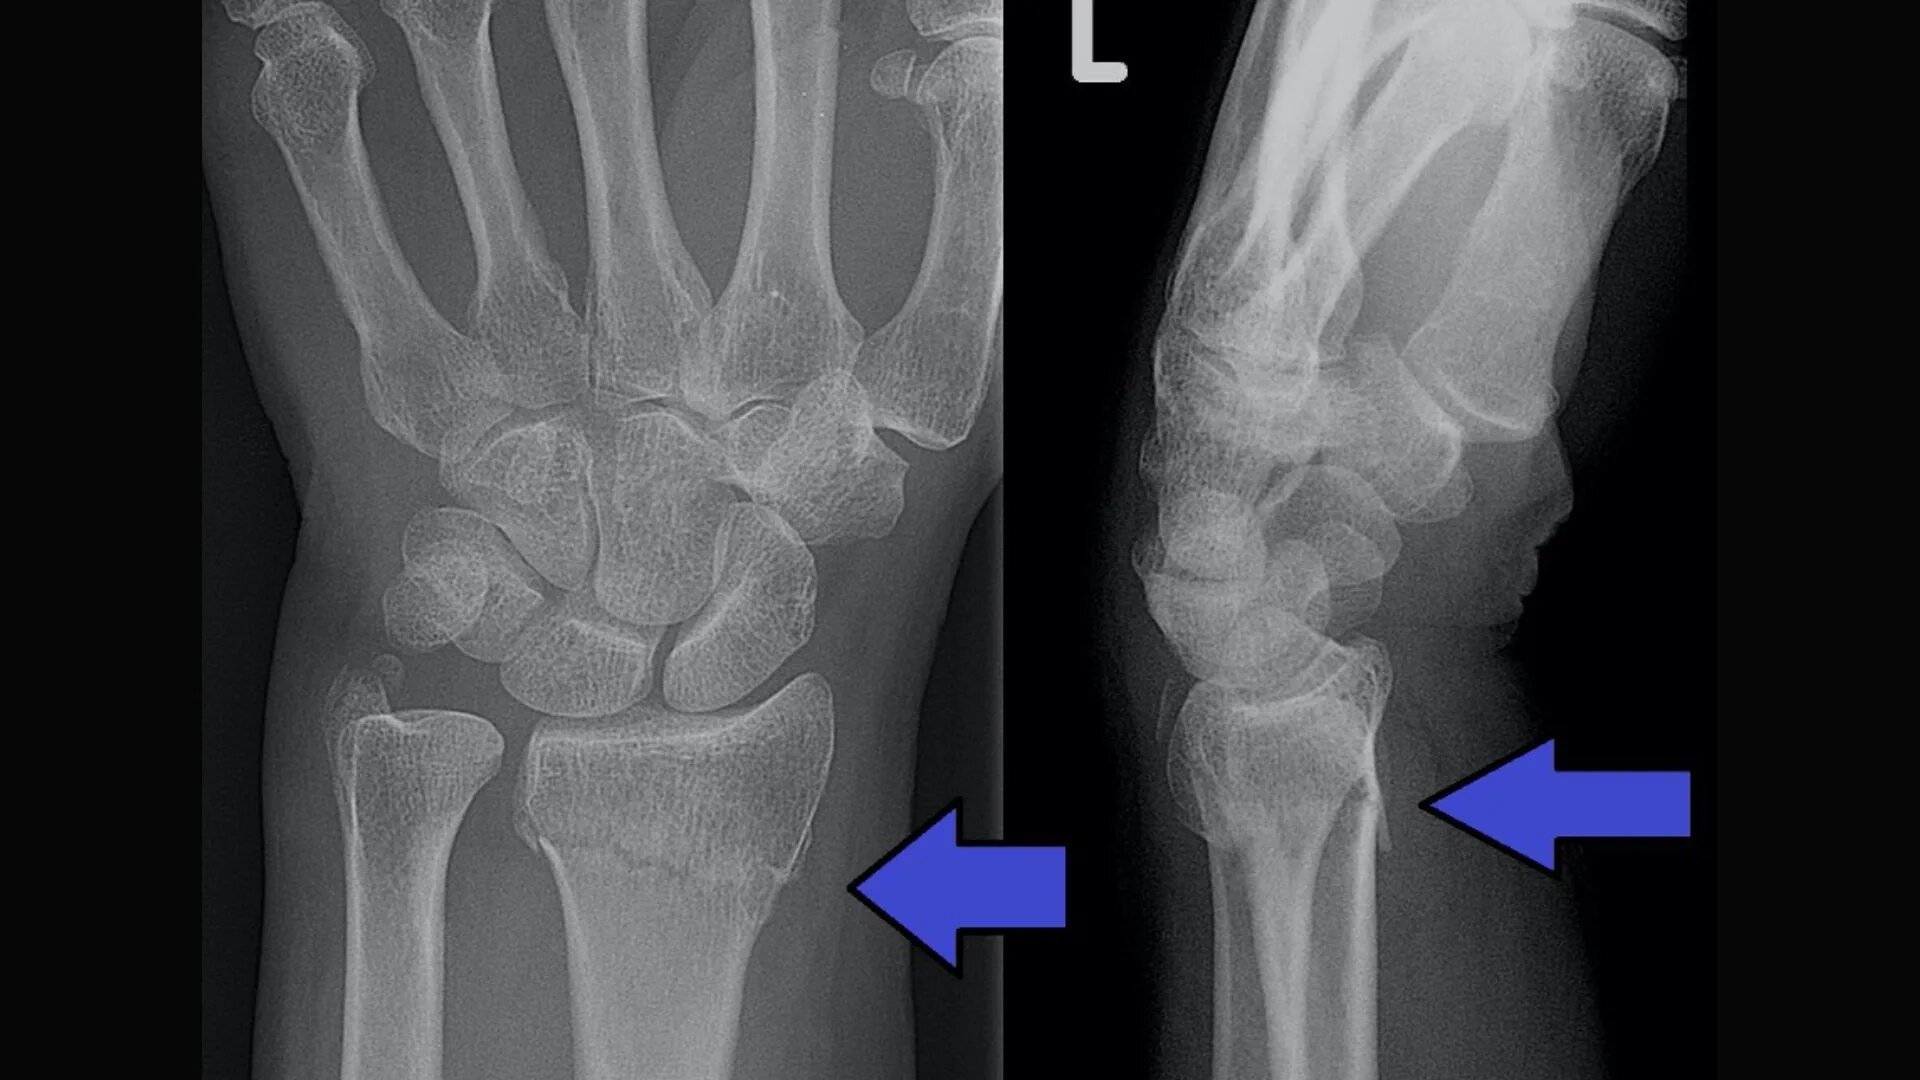

Перелом руки срок срастания